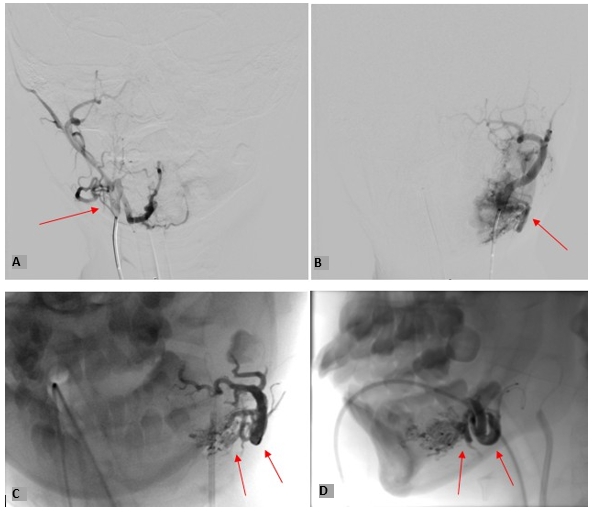

Cerebral Angiography as shown in Figure 6, followed by embolization of left mandibular AVM was undertaken as shown in Figure 7. At the end of the procedure, immediate brisk bleeding ensued requiring major haemorrhage protocol activation with infusion of 270 ml of red blood cells, 400 ml of octaplas (a form of FFP) and 500 ml of Hartmann’s solution, in theatre. Following, approximately 1 litre of blood loss, bleeding was controlled with gauze soaked with adrenaline and tranexamic acid and patient was transferred to Paediatric Intensive Care Unit (PICU) post-procedure.

Figure 6: Showing Selective Angiography of

A) Right Internal Carotid Artery, B) Left Internal Carotid Artery. C) Coronal view and, D) Sagittal view of large left mandibular AVM with a massive varix within the bone.

Figure 7: Embolisation of Mandibular AVM (Transarterial Embolization Through Facial, Lingual and Mandibular Branches)